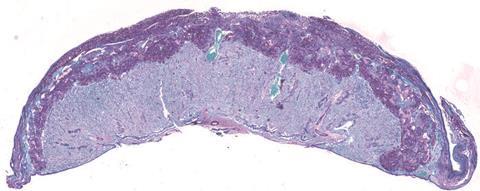

In a study in mice, the researchers compared the placentas of mice with no gut bacteria to those of mice with Bifidobacterium breve in their gut during pregnancy.

In the study, over 150 biological processes in the placenta - involving over 400 different proteins - were found to be different in mice with, and without, Bifidobacterium breve in their gut.

The mice with Bifidobacterium breve in their gut lost fewer of their pregnancies. Their placentas were better at absorbing and transporting nutrients, like amino acids and lactate, from mother to fetus - vital for fetal growth. Their placentas also produced more of the hormones important for pregnancy, such as prolactins and pregnancy-specific glycoproteins.